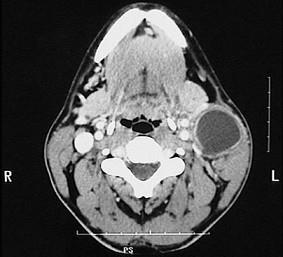

问题 40岁女性,右上颈部包块发现5年,增长不明显。近3天发生上呼吸道感染,肿物突然增大,伴疼痛。检查见肿物位于胸锁乳突肌上1/3前缘,质软,有波动感,无搏动,体位试验阴性。CT 检查如图。最可能的诊断是 ( )

选项 A.海绵状血管瘤 B.囊性水瘤 C.鳃裂囊肿 D.神经鞘瘤 E.甲状舌管囊肿

答案 C